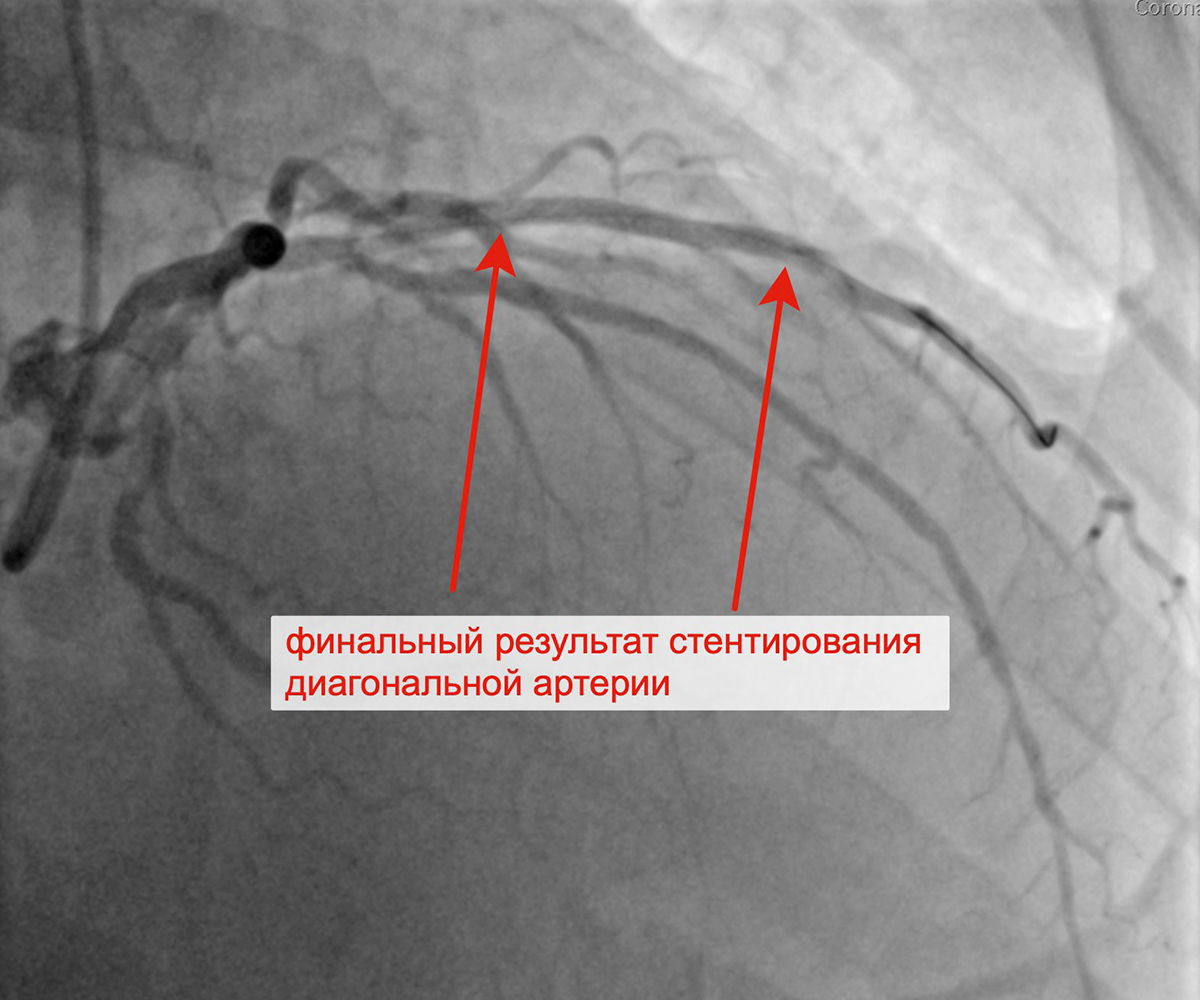

Вторым этапом в январе 2023 г. принято решение о проведении пациенту с персистирующей формой ФП, ГКМП, сохраняющейся клиникой стенокардии напряжения, известной коронарной анатомией, многососудистым поражением коронарного русла баллонной ангиопластики и стентирования крупной диагональной артерии (ДА) (1 стент с лекарственным покрытием). При контрольной ангиографии: стент и ДА проходимы, позиционирование стента адекватное, диссекции или остаточного стеноза в стентированном сегменте ДА нет, кровоток TIMI 3 по ДА и всем ее ветвям.

Стенозы диагональной артерии Выполнена баллонная ангиопластика ДА

Выполнено позиционирование и имплантация стента в ДА Финальный результат стентирования ДА